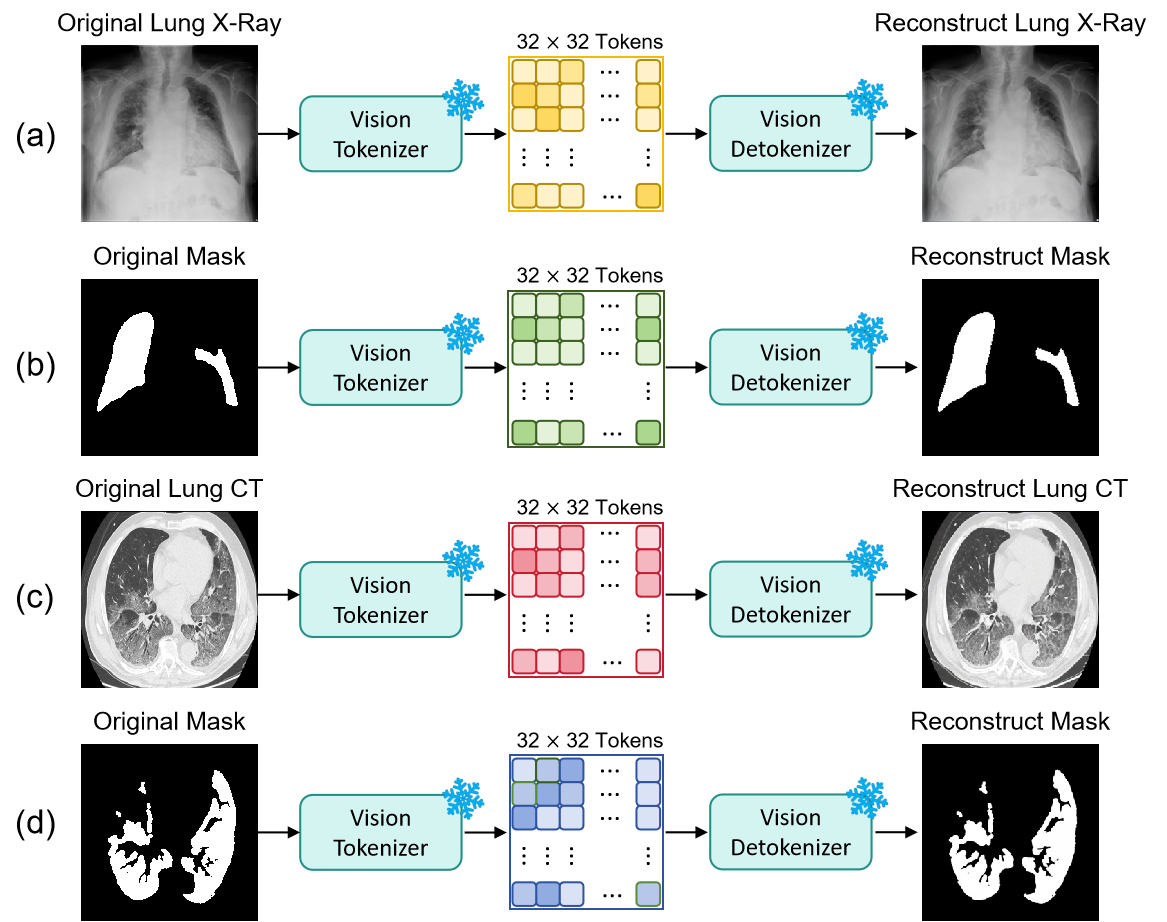

3.1.1 Vision and Text Tokenizer

We employ the vision tokenizer based on Emu3 SBER-MoVQGAN[40], which achieves 88 spatial compression and supports arbitrary spatial resolutions. Specifically, a 256256 medical image is encoded into a 3232 grid of discrete tokens, each selected from a codebook of size 32,768. To demonstrate the suitability of this general-purpose tokenizer for medical imaging tasks, Fig. 3 shows examples of medical images and corresponding segmentation masks that are first tokenized and then reconstructed from tokens. The reconstructed results confirm that critical structural details and edge textures are well preserved, validating the effectiveness of the Emu3 tokenizer for MRIS. And we use Qwentokenizer[41] for medical descriptions.